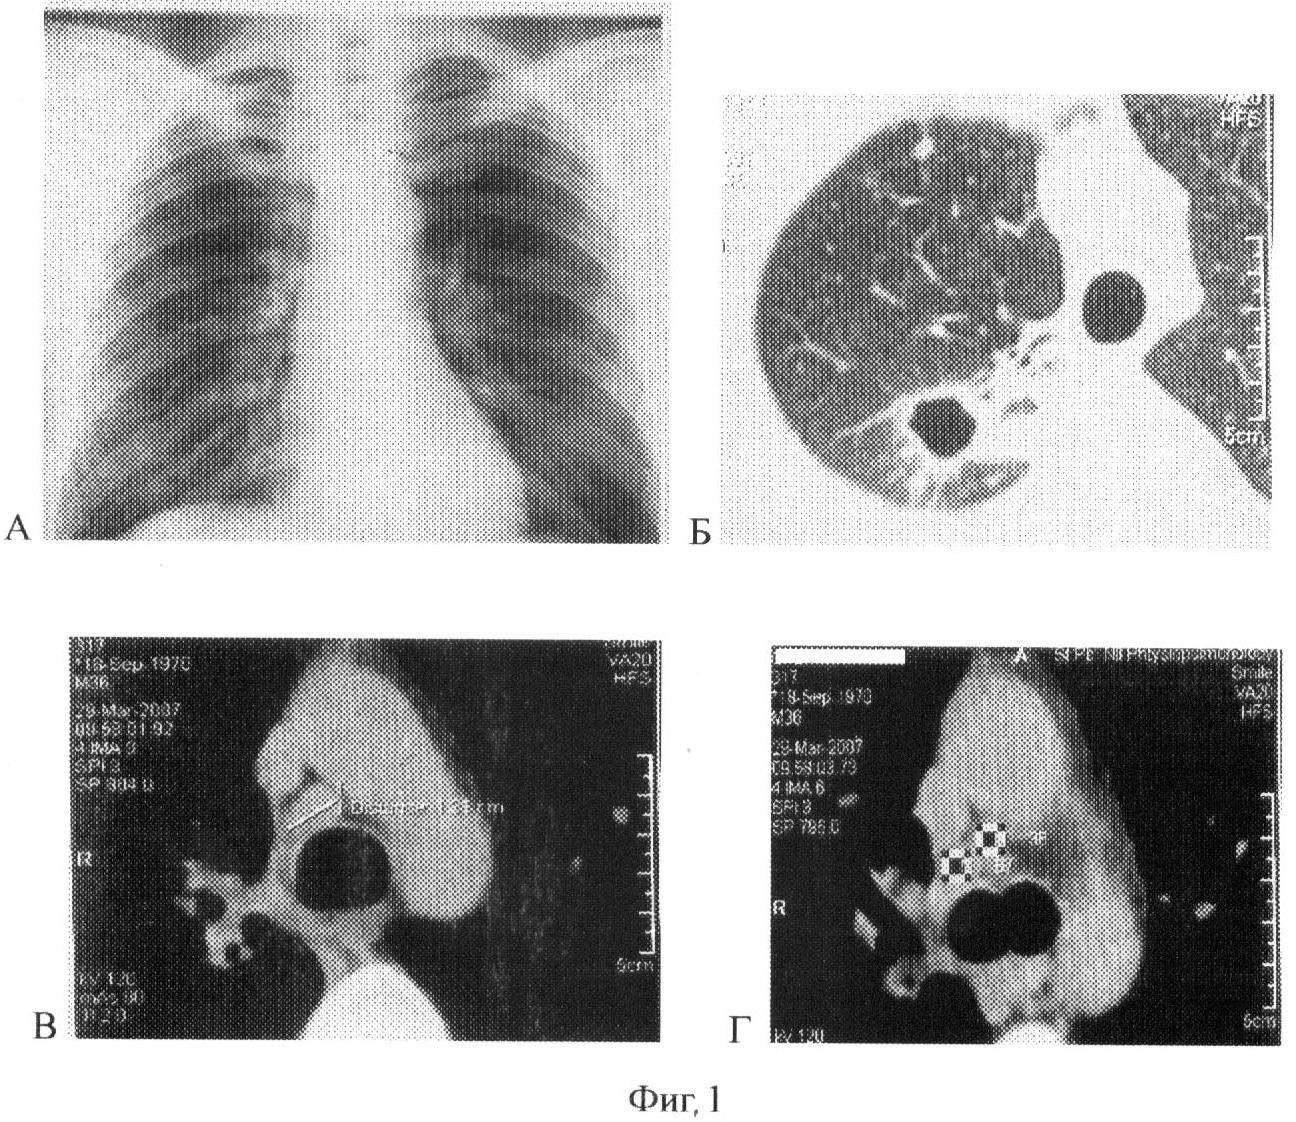

Сущность предлагаемого изобретения представлена на фиг.1, 2 и 3. На фиг.1 – данные рентгенологического обследования больного (пример 1), на фиг.2 и 3 – данные рентгенологического обследования больного (пример 2).

2. Больная Н., 16 лет, поступила 27.09.2005 с диагнозом инфильтративный туберкулез верхней доли правого легкого в фазе распада и обсеменения БК+. Из анамнеза известно, что заболевание выявлено в сентябре 2005 года при прохождении профилактического обследования. Из семейного тубконтакта с отцом. При поступлении состояние удовлетворительное, жалоб нет. В клиническом анализе крови отмечается повышении СОЭ до 16 мм/ч. Серологические реакции на туберкулез отрицательны. По данным реакции Манту с 2 ТЕ инфицирована с прошлых лет. Посевом от 28.09.05 выделена культура микобактерии туберкулеза, чувствительная ко всем препаратам.

При рентгенологическом обследовании в момент поступления (Фиг.2-А, Б) определяется в верхней доле правого легкого на фоне разнокалиберных очагов полость распада (каверна) диаметром 1,8 см с неравномерно утолщенной стенкой. При СКТ (Фиг.2-В, Г) дополнительно визуализируются увеличенные лимфоузлы нижней правой паратрахеальной и бифуркационной группы до 1, 2 см. Структура лимфоузлов не изменена.